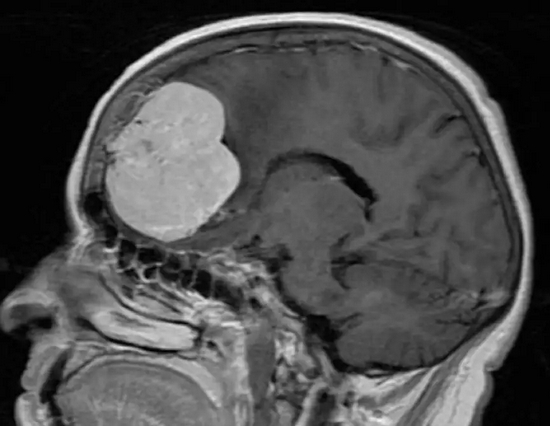

2、颅内占位

脑瘤有良恶性之分,恶性发展快,病程短,神经系统症状逐渐出现,并且进行性加重,带瘤存活 20 余年的可能性微乎其微。

脑胶质瘤

良性发展慢,病程长,患者可以没任何症状,也可以随着肿瘤生长,影响到脑部血液循环,阻塞脑脊液的循环通路,造成颅内积水或脑水肿,甚至会发生脑疝,危及生命。

虽然良性肿瘤存活期可能大于 20 年,但症状应进行性加重,不会以反复发作、不残留神经功能障碍为表现。

同样,我们也不能以华佗想要用斧子砍开头颅进行手术,便断定曹操先生一定就‘脑壳有包’。

脑膜瘤